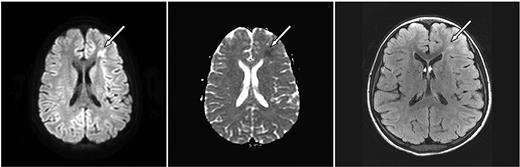

Axial MRI images of case 3. A 10-year-old girl with SCD and parvovirus infection with hgb = 2.9 g/dL showing (left, arrow) an area of restricted diffusion on DWI images with an ACD correlate (middle). Follow-up FLAIR MRI 7 months later (right) shows a lesion corresponding to the affected area on the DWI.

ASCIE were identified by DWI in 4 (18.2%) of 22 children with SCD and 2 (6.7%) of 30 without SCD (P = .382, Table 1). All had areas of restricted diffusion on DWI with corresponding areas of decreased signal on ADC map. There were corresponding abnormalities on the initial FLAIR images in 4 of 6. DWI lesions were subcortical or in the deep white matter (Figures 1–2). One patient had deep white matter DWI lesions and a lesion in the splenium of the corpus callosum without history of seizure. Two of the 6 patients had multiple DWI lesions, 4 had solitary lesions.

Follow-up MRI studies (Figures 1–2) were obtained 2.5 to 7 months later for other clinical indications for 4 of 6 of the patients with ASCIE; 3 had lesions on FLAIR images consistent with SCI in locations corresponding to the ASCIE on the initial study MRI (Table 1) and thus meet the definition of acute SCI. All 3 had SCD. Notably, the patient without a corresponding lesion on follow-up imaging also had no FLAIR correlate on the initial study MRI. This patient did not have SCD. We believe this to be a transient, reversible ASCIE.7 Magnetic resonance angiography (MRA) was not part of our study protocol but was obtained for the clinically indicated follow-up studies for 4 of 6 of the patients with ACSIE and was normal in 3, with 1 patient demonstrating subtle vascular irregularities in the internal carotid artery and middle cerebral artery ipsilateral to the ASCIE (Table 1).